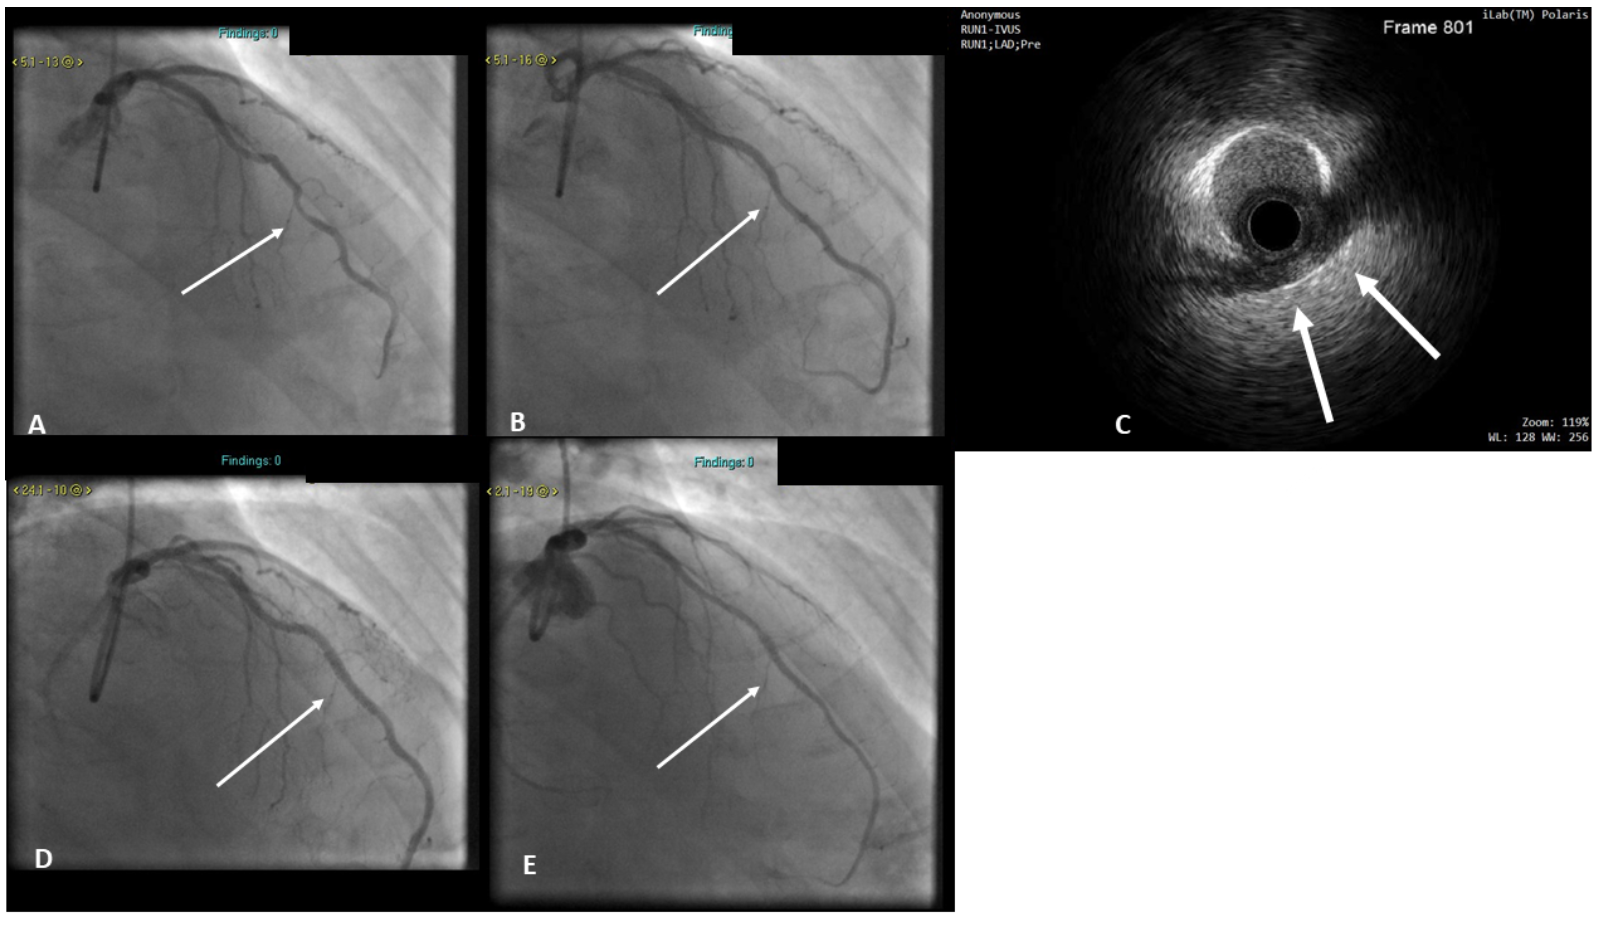

Patient 3. A 50-year-old patient presented with typical exertional angina. Coronary angiography demonstrated a mid-LAD MB. He was initially treated conservatively, but his symptoms persisted despite maximally tolerated antianginal therapy and he was readmitted for invasive ischemia testing and consideration for PCI. Physiological functional testing revealed an RFR value of 0.74 and FFR of 0.70. The LAD MB segment was therefore stented with a 3.0- x 28-mm DES and postdilated with a 3.5-mm NC balloon with optimal angiographic and IVUS result (Figure 3). The RFR value rose to 0.92 and the FFR to 0.93 post PCI. At 12-month follow-up, the patient has had no recurrent symptoms and is angina free. At 18 months post procedure, he developed atypical chest pain. Subsequent coronary angiography showed a widely patent stent in the LAD with no restenosis (Figure 3). His symptoms have subsequently resolved.